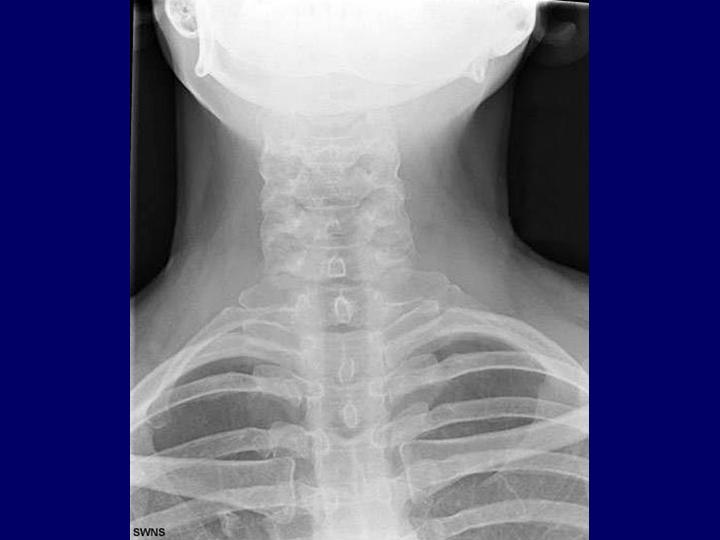

Síndrome del Opérculo Torácico

Cirugía Cardíaca

| Autor: Leandro Revello Chiang